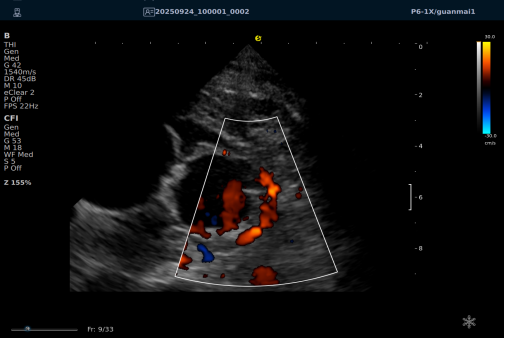

一例胸闷患者,临床采用无创冠脉超声作为初步评估手段,检查中发现:

彩色多普勒:敏感捕捉到局部血流加速现象;频谱多普勒:测得峰值血流速度明显升高,频谱形态异常。

彩色多普勒动态图

彩色多普勒

基于超声提示的异常发现,临床为患者安排了冠脉CTA检查,结果显示前降支近段存在约45%狭窄,与超声提示的血流动力学改变高度一致。

这一病例体现了冠脉超声作为初筛工具的重要价值:它能够无创、实时地评估冠脉血流动力学状态,为后续是否需要进一步影像检查提供重要参考。超声与CTA的协同应用,既能评估结构变化,又能反映功能状态,为临床诊断提供了更全面的信息。